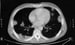

How Would You Treat This Older Patient's Pneumonia?

A 75-year-old man develops fever, chills, and a cough. His history is significant for coronary disease, hypertension, and a 4-cm aortic aneurysm. He has been successfully treated for prostate and colon cancer. He reports that he is allergic to amoxicillin, noting that he developed a rash when taking the drug about 20 years ago. His current medications are atorvastatin, amlodipine, lisinopril, and aspirin.